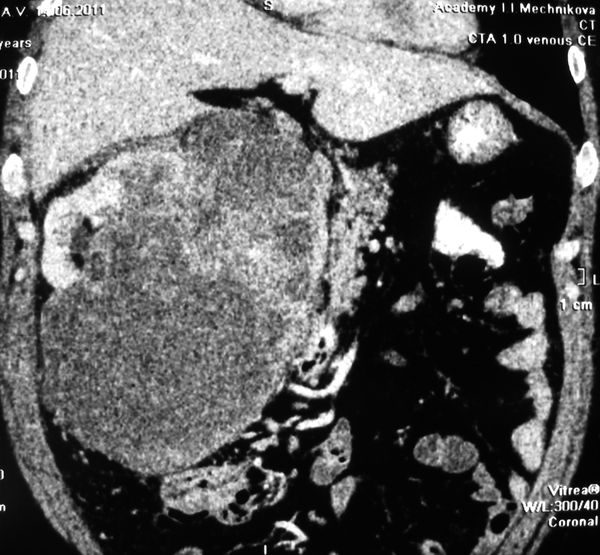

Огромная опухоль правой почки

Гигантская опухоль правой почки. Экстримальная нефрэктомия.